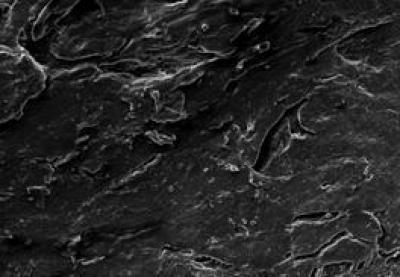

Under scanning electron microscope, in poly(lactic-co- glycolic acid) tube group, nerve fibers were poorly arranged, morphological changes to the nerve fiber surface connective tissue, endoneurium, myelin sheath and axons were observed, and vessels of the basilar membrane were occluded by fragmented axonal and myelin sheath tissue.

(Photo Credit: Neural Regeneration Research)